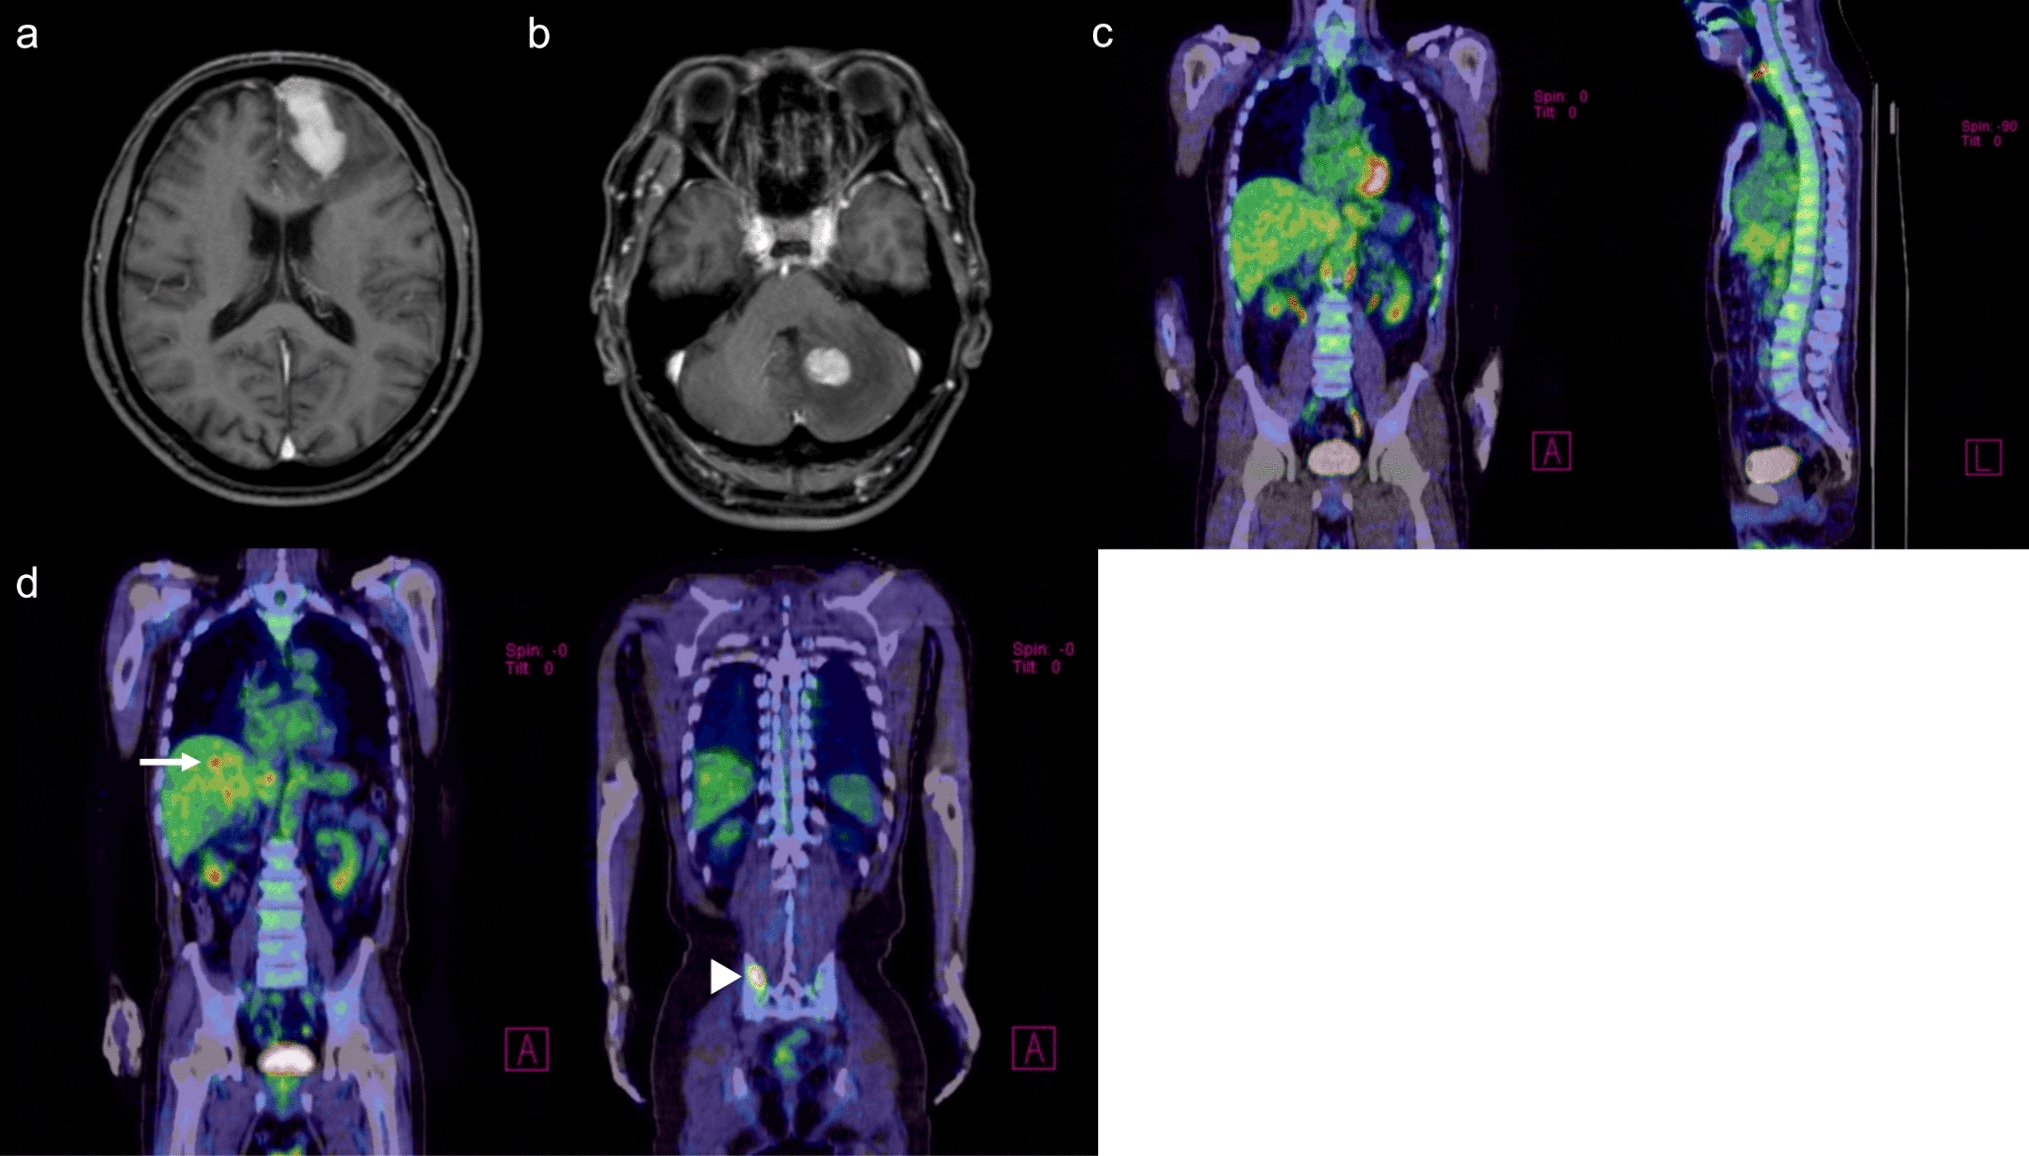

Chen Y, Tian T, Guo X et al (2020) Polymorphous low-grade neuroepithelial tumor of the young: case report and review focus on the radiological features and genetic alterations. BMC Neurol 20:123